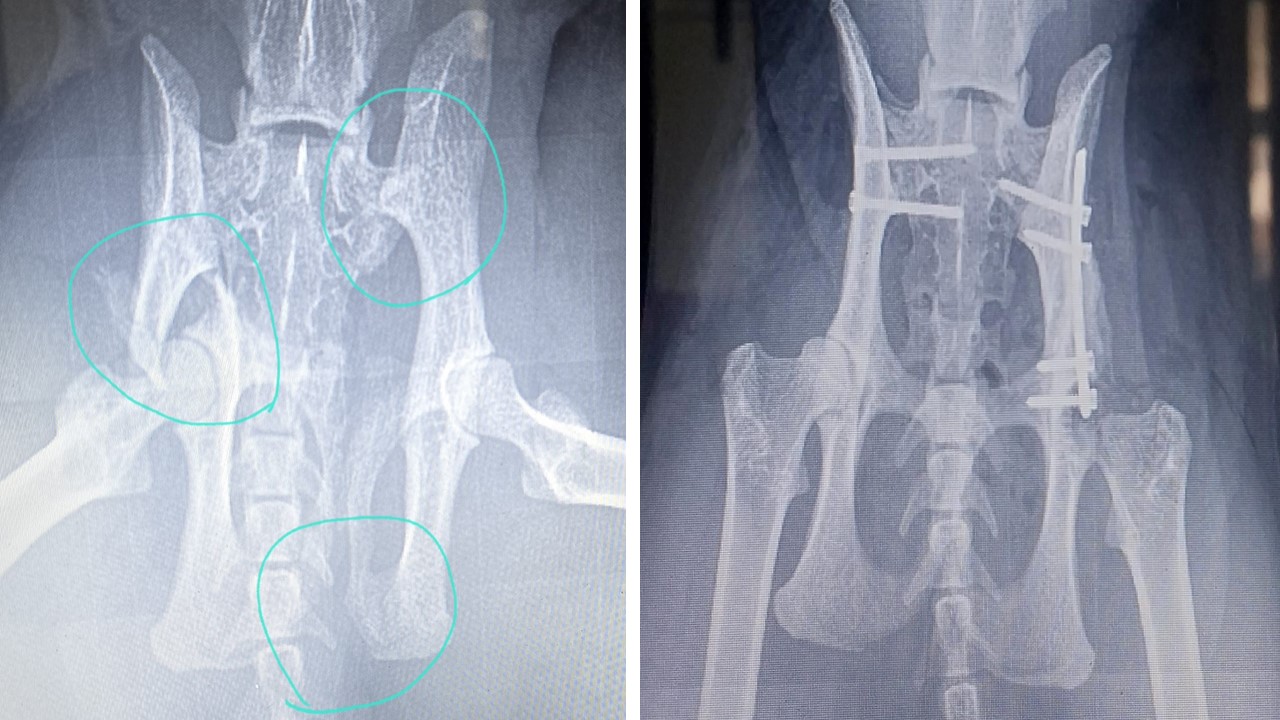

Kliniğimizde, ortopedi alanında uzman hekimimiz eşliğinde birçok operasyon başarıyla gerçekleştirilmektedir. Ortopedik hastalıklarda doğru tanı büyük önem taşır. Bu nedenle, kliniğimize başvuran her hastanın ortopedik şikayetleri, özel uzmanlık alanı cerrahi ve ortopedi olan Op. Uzman Veteriner Hekim Mehmet TABUR tarafından değerlendirilir. Hastanın ihtiyaçlarına en uygun tedavi veya operasyon planı titizlikle oluşturulur. Kliniğimizde tüm ortopedik operasyonlar rutin olarak uygulanmakta ve her işlemde yüksek hijyen ve dikkat standartları korunmaktadır.

Uygulanan Ortopedik Operasyonlardan Bazıları:

• Kalça çıkığı (Luxatio Femoris)

• Ortopedik plak teknolojisi (İnternal fiksasyon plakları)

• Çapraz bağ kopuğu tedavisi

• Dirsek çıkığı (Luxatio Cubiti)

• Patella çıkığı (Luxatio Patella)

• Kas ve tendon yaralanmaları

• Eksternal fiksasyon ile kırık tedavisi

• Atel ile fiksasyon uygulamaları

• Intrameduller pin ile kırık tedavisi

• Omuz çıkığı

• Sakroiliak ayrılma

Her vakada hasta konforu ve uzun vadeli sağlığı ön planda tutulur. Operasyon sonrası iyileşme süreci de veteriner hekimlerimiz tarafından yakından takip edilmektedir.